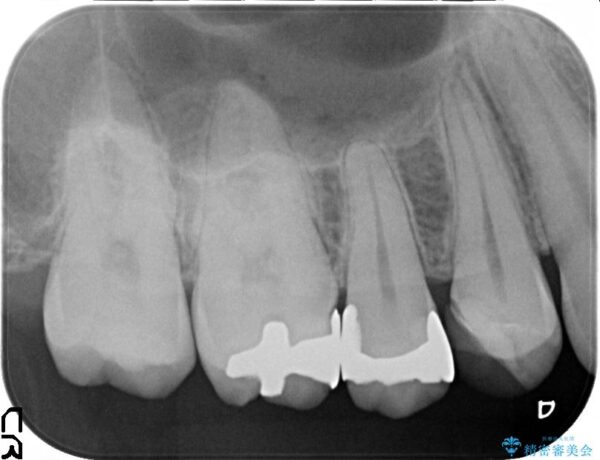

銀歯を除去し、審美性を改善、虫歯の再発リスクも低いセラミックインレーを用いた治療計画を進めていきます。

セラミックインレーは審美性に優れるだけでなく、表面の物性が劣化しにくいこと、適合に優れることで虫歯の再発リスクが銀歯よりも優位に低くなります。